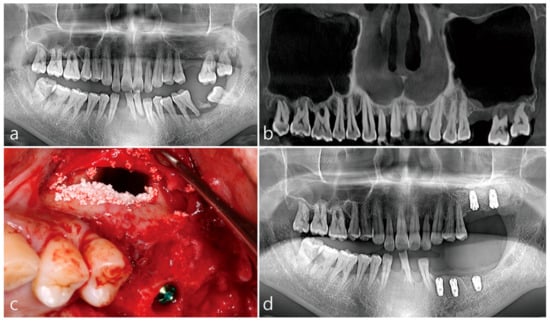

A 43-year-old male smoker visited the private clinic due to severe tooth mobility and chewing discomfort. On the pre-operative panoramic radiography, alveolar bone resorption was very severe due to advanced periodontitis and the height of residual bone was about 1–2 mm. Maxillary upper left, first molar tooth was missing (Figure 1a). A panoramic image of the preoperative CBCT showed no thickening of the left and right maxillary sinuses and severely pneumatized sinus (Figure 1b). During the lateral window approach for sinus floor elevation, the Schneiderian membrane was widely perforated during sinus floor elevation and the lateral bone lid was pushed up while attached to the sinus membrane. Implant site preparation was performed before filling the bone graft substitute. The osteotomy site was undersized drilled. Bone grafting using Osteon III (Genoss, Suwon, Korea) was performed on the sinus floor and the upper part of the lateral window was opened. Two 4.8 × 10 mm implants (Implantium, Dentium, Suwon, Korea) were installed (Figure 1c). On panoramic radiography taken immediately after surgery, bone graft substitute supporting the implants on the sinus floor was observed (Figure 1d). Patient reported minimal nasal bleeding and moderate facial swelling until 3 days after surgery. No other clinical events were reported during the healing process. Second stage surgery for uncovering of implants was performed 6 months after surgery. Implant placed at left upper second molar osseointegrated, but the implant at the left upper first molar was removed due to loss of osseointegration and immediately replaced with a wider 6.0 × 10 mm implant. On the coronal image of the left maxillary sinus CBCT before surgery at the first molar site, no sinus membrane thickening was noted, and the thickness of the buccal bone was thin (Figure 1e). Coronal image of CBCT immediately after MSA shows it in a state in which the Schneiderian membrane is irreparably perforated. A space between the elevated lateral bone lid and the sinus graft was observed, and displacement of the bone graft particles was not observed (Figure 1f). In the coronal image of CBCT 7 days after surgery, there was no leakage of bone graft substitute, and the sinus membrane thickening was insignificant (Figure 1g). The upper left maxillary first molar implant was uncovered after 4 months. At this time, the flap was reflected up to the opened lateral window site. The open lateral window site was closed with regenerated bone (Figure 1h). After 2 months of uncovering, the splinted prosthesis was delivered. In the CBCT taken immediately after the prosthesis delivery, the bone graft substitute was well consolidated without displacement and no volume change was observed (Figure 1i). In addition, the continuity of the buccal bone contour was well maintained at the lateral window site (Figure 1i). After 1 year follow-up, the patient’s chewing function was well maintained and no sinonasal complications were noted. No loss of marginal bone was observed on the panoramic radiograph (Figure 1j).

Figure 1.

Case 1. Preoperative and postoperative radiographic findings of case 1, and clinical pictures of the open lateral window technique. (a) On the preoperative panoramic radiograph, advanced periodontitis was accompanied by severe alveolar bone loss; (b) A panoramic image of the preoperative CBCT showed no thickening of the left and right maxillary sinuses; (c) The sinus membrane was widely perforated during sinus floor elevation. Bone grafting was performed on the sinus floor and the upper part of the lateral window was opened; (d) Panoramic radiograph after MSA and implant placement at the same time. (e) On the coronal image of the left maxillary sinus CBCT before surgery, there was no sinus membrane thickening and the thickness of the buccal bone was thin; (f) Coronal image of CBCT immediately after MSA in a state in which the maxillary sinus membrane is widely perforated. No leakage of bone graft substitute was found; (g) Coronal image of CBCT 7 days after surgery. There was no leakage of bone graft substitute, and the maxillary sinus membrane thickening was insignificant; (h) After 6 months of operation, uncovering was performed by tissue punching method, but explanation was performed due to osseointegration loss of implant #26, and re-implantation was performed immediately with a Ø 6.0 × 10 mm. At this time, the previous lateral window site was confirmed by reflecting a buccal mucoperiosteal flap. The exposed window site was completely covered with bone; (i) The prosthesis was delivered 4 months after the #26 implant re-implantation; (j) One year after the final prosthesis was installed, panoramic radiography showed that most of the bone graft substitute remained, and resorption of marginal bone around the implant was not observed.